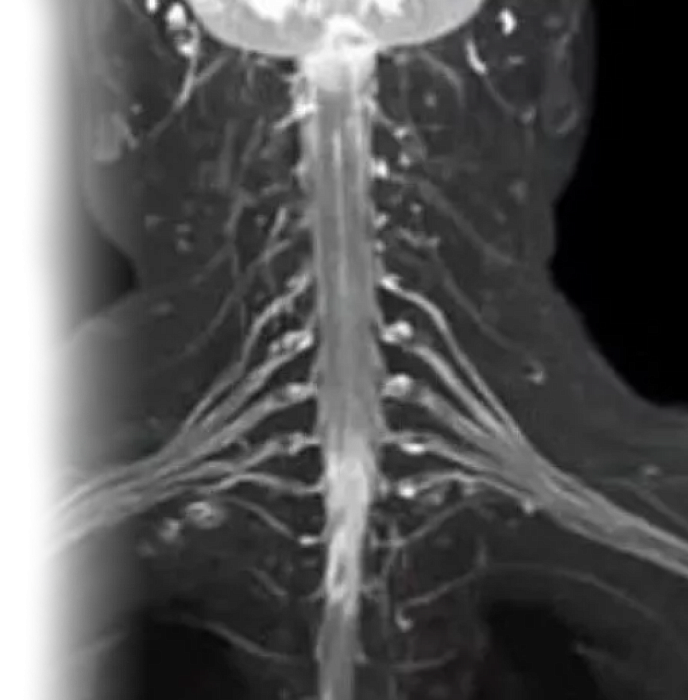

Также есть возможность провести МРТ плечевого сустава с использованием дополнительных последовательностей и МРТ плечевых сплетений.